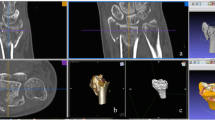

There are small variations in indications depending on patients’ demographics and surgeon preference. The top indications for 3D printing are visualization of complex articular (Fig. 1) and acetabulum fractures. Shaft fractures are less commonly indicated. Patient-specific osteotomy guides (Fig. 2) and shoulder replacement guides are common in three centres. Patient-specific fracture fixation implants are used in two centres.

The digital workflow is technically demanding and requires trained staff [13]. Segmented digital models are suitable for printing only after optimization. The main optimization steps are trimming, hole filling and stamping of identity information. Overzealous filling of gaps and oversimplification of the model to facilitate the manufacturing process may lead to loss of fidelity and details. Training frontline physicians can facilitate off-hours printing for urgent cases. Patient-specific instruments require specialized personnel highly familiar with digital planning and the surgical procedure. The surgeon becomes more familiar with the treatment when personally involved in the digital workflow. Validation of digital models and plans should be carried out with surgeons before printing (Fig. 5).

Fracture model fabrication requires a balance between preserving important fracture detail and removing complex intramedullary and cancellous structures. Figures show estimated production time and material usage using an industrial fused deposition modelling (FDM) printer (Fortus 450mc, Stratasys, Eden Prairie, MN, USA)